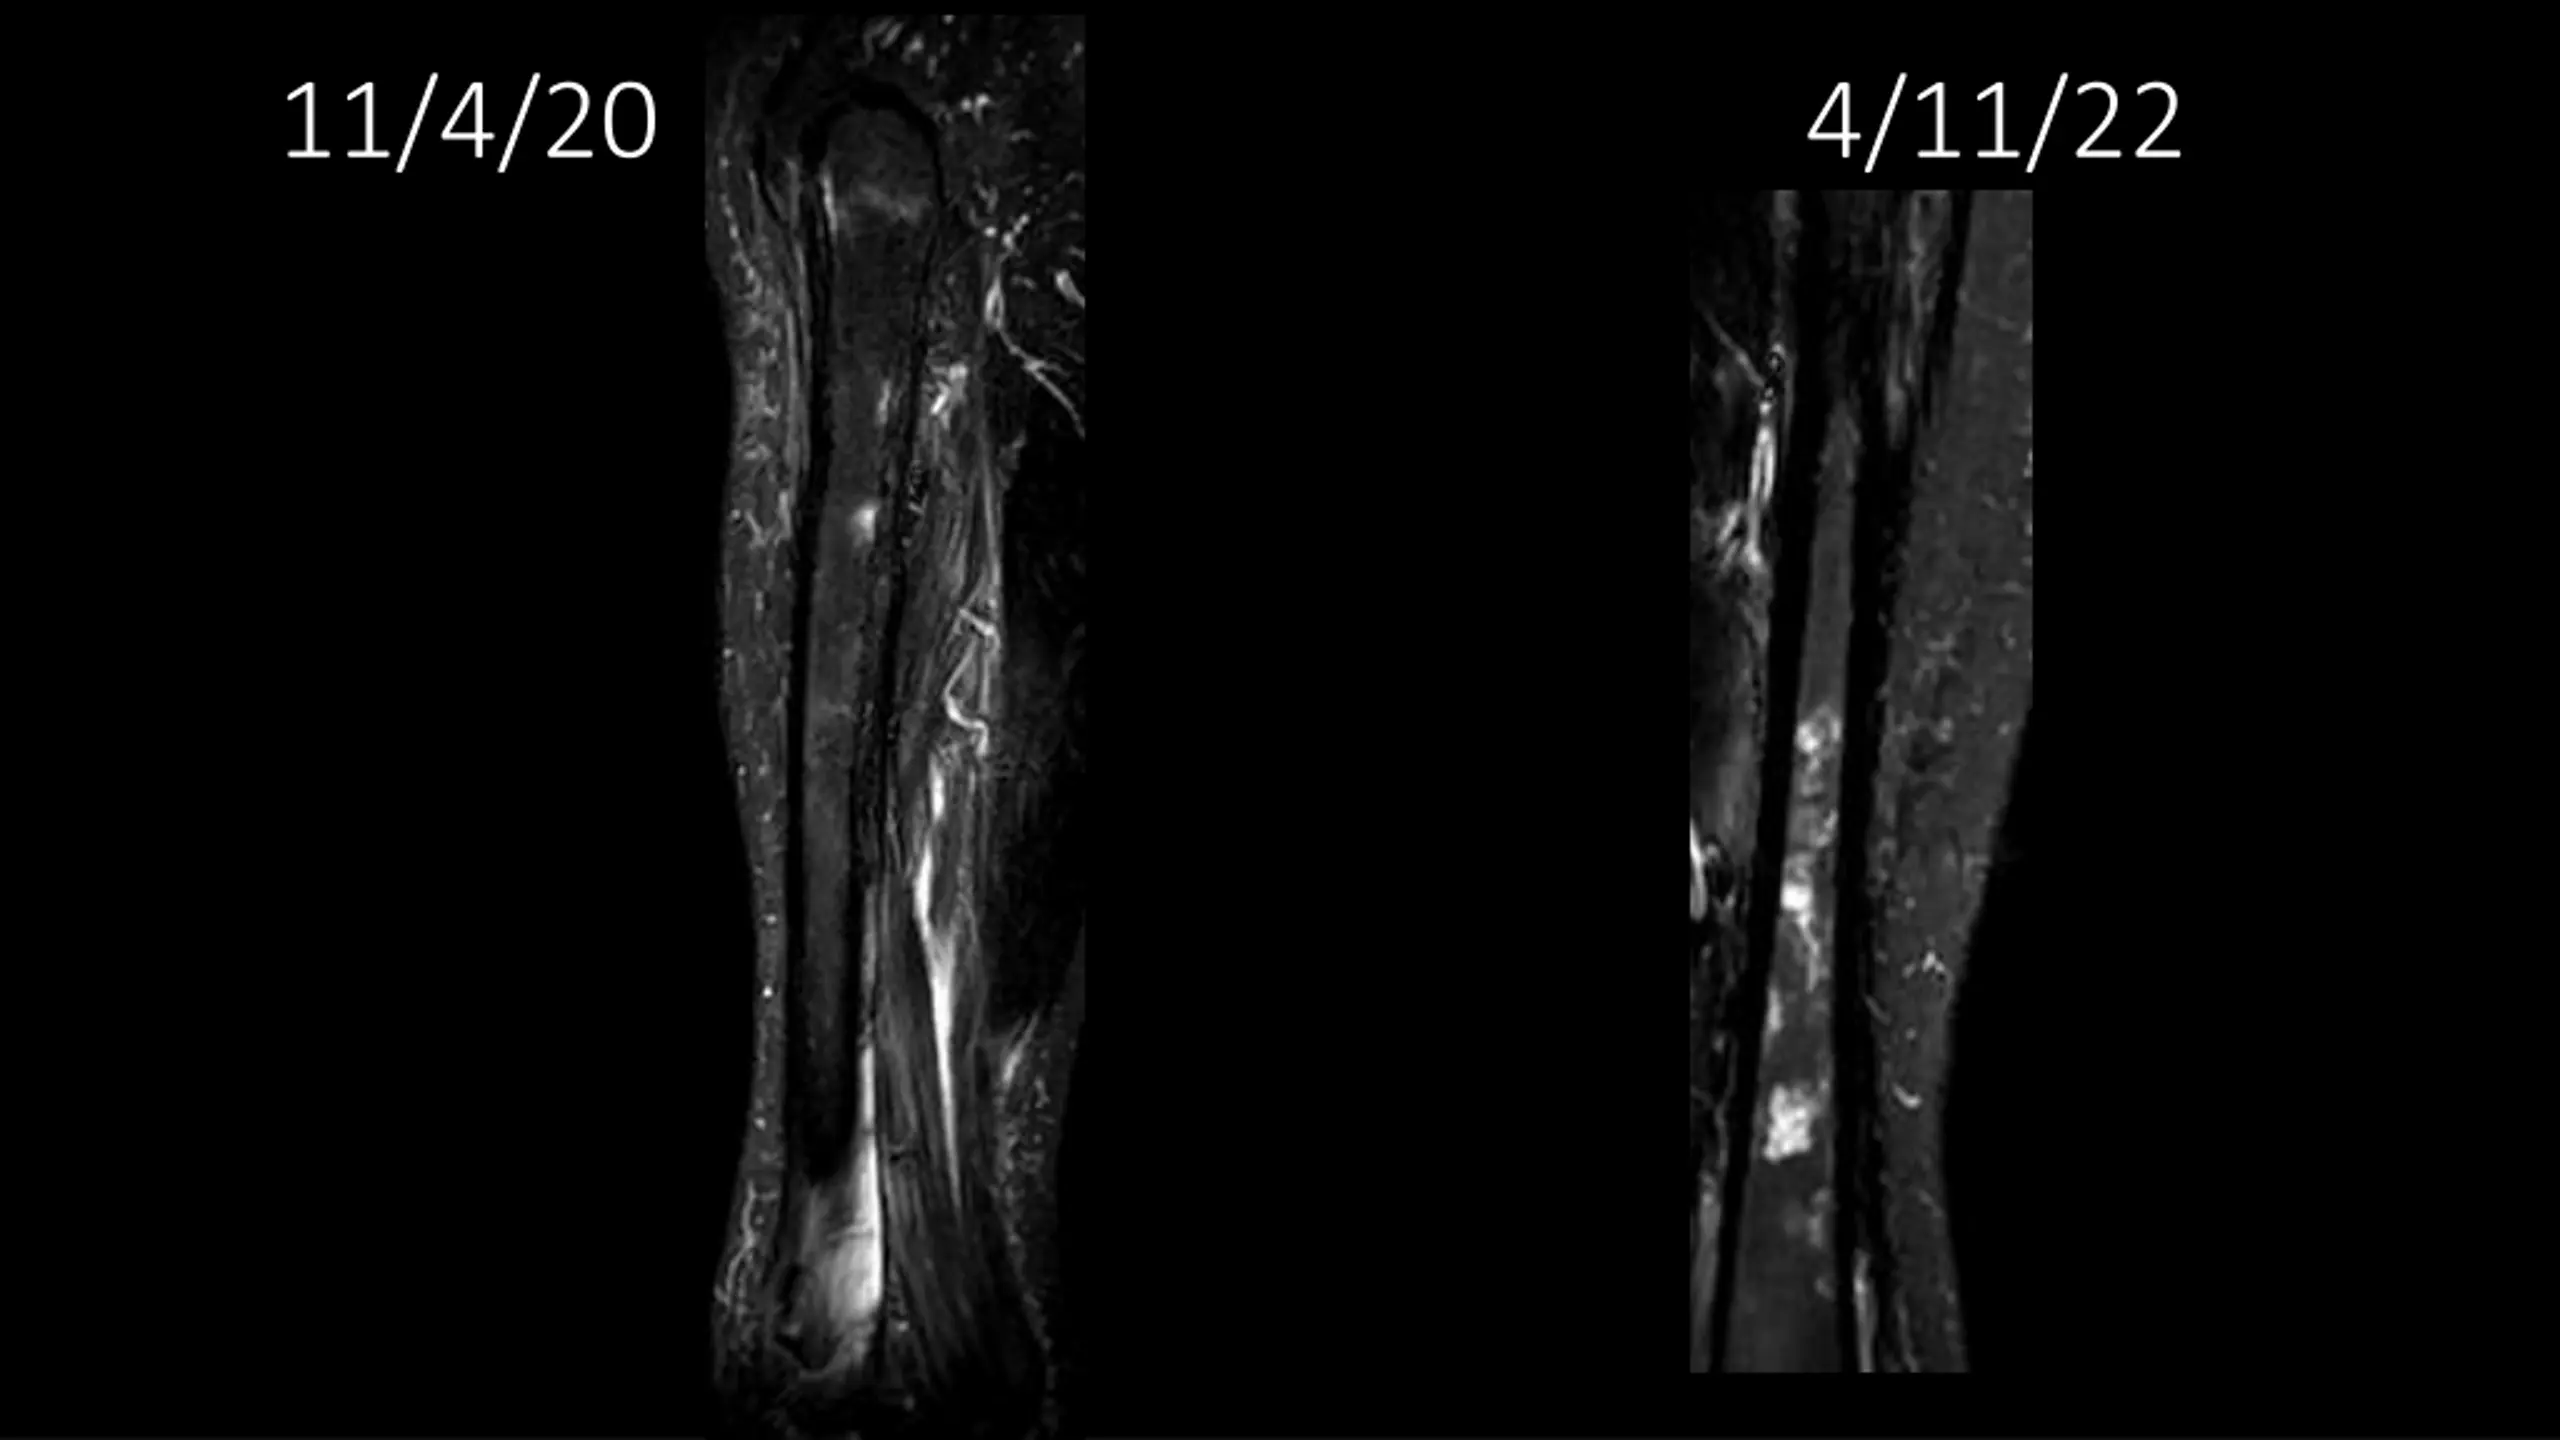

62-year-old shows post-surgery progress from 11/4/2020 to 4/11/22

Explore the journey of a 62-year-old individual post-UPS resection on 11/4/2020, through a series of dated images leading up to 4/11/22. Witness the transformation and recovery process in these visual updates reflecting the progression over time.